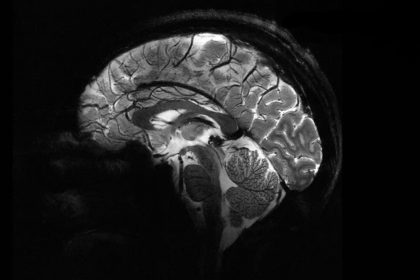

قدرتمندترین دستگاه MRI جهان اولین اسکن مغزی خیرهکننده را ثبت کرد.

به گزارش رسانه مدیاتی، قدرتمندترین دستگاه MRI جهان با اسکن مغز انسان زنده شروع به اثبات ارزش خود کرده است. تصاویر به دست آمده یک نگاه اجمالی با وضوح فوقالعاده بالا به مغز میدهند که به ما در درک بهتر ماهیت هوشیاری و درمان بیماریهای عصبی کمک میکند.

مزیت اصلی این قدرت اضافی این است که میتوان تصاویری با وضوح بسیار بالاتر از مغز را بسیار سریعتر گرفت. تنها در چهار دقیقه، Iseult میتواند تصاویری تا 0.2 میلیمتر از بافت مغز را به صورت افقی، در برشهایی به ضخامت 1 میلیمتر ثبت کند. این حجم معادل چند هزار نورون در یک زمان است.

تصاویر مقایسه ای از مغز انسان که با دستگاه جدید Iseult MRI در سطوح مختلف قدرت گرفته شده است. همه این تصاویر در مدت زمان یکسانی گرفته شدهاند و نشان میدهد که چقدر میتوان جزئیات بیشتری را با آن گرفت.

Iseult چند سال پیش روی کدو تنبل آزمایش شد، اما اکنون اولین مغز انسان خود را که متعلق به 20 داوطلب سالم است، اسکن کرده است. این تصاویر خیرهکننده پتانسیل فناوری جدید MRI را نشان میدهد تا اطلاعاتی را که قبلاً دستنیافتنی بود، در مورد نحوه عملکرد مغز از جمله نحوه رمزگذاری بازنماییهای ذهنی و علائم عصبی مرتبط با خودآگاهی را نشان دهد.